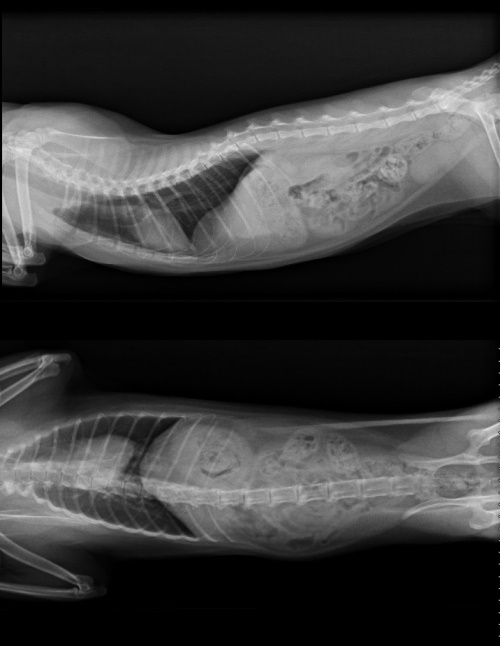

前陣子溫泉君的眼睛分泌物又開始增多,就醫檢查發現淋巴腫大,進一步抽血檢驗、超音波檢查,懷疑可能是心臟肥厚,醫師建議轉診心臟專科檢查,轉診檢查並無明顯心雜音,X光也無看出明顯異狀,心臟超音波檢查,確診溫泉君的確有心臟肥厚等問題,心臟舒張和收縮的能力較差,心臟肌肉變厚,血液進入心臟的量和壓縮量會越來越少,舉例說明,每次收縮血氧是1,因心臟肥厚每次只有0.8,若要維持100,正常需收縮100次,而心臟肥厚需收縮125次,心跳會越來越快,必須進行治療,但也有可能在治療情況下發生猝死,醫師建議要盡量讓溫泉君保持心情平穩、愉快,減少環境變動,每天按時服藥,才能夠有好的生活品質,心臟專科檢查費用還請各位幫忙。